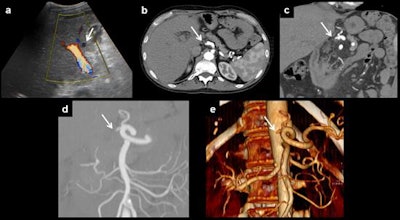

Color Doppler ultrasound exams are routinely performed at 24 to 48 hours on the seventh day, the first and third month after transplantation, while CT and MR images are acquired based on the Doppler ultrasound findings even in the absence of abnormal liver function, they explained in an in-depth article posted on 14 August by Insights into Imaging.

Because vascular complications appear early after surgery, Doppler ultrasound should be performed by experienced staff; diagnostic angiography is seldom performed.

The main imaging findings in patients after liver transplantation are hepatic artery complications (such as thrombosis, stenosis of the anastomosis, and pseudoaneurysms), portal vein abnormalities (such as occlusion and stenosis), and hepatic veins and/or inferior vena cava flow changes (Budd-Chiari syndrome).

The most frequently affected anastomosis is at the hepatic artery, they continued. This anastomosis can be made in different places, but the two most frequent are in the hair-pin space between the right and left hepatic arteries of the recipient or at the outlet of the gastroduodenal artery.

"Stenosis may progress to thrombosis. So, stenosis and thrombosis are two entities of the same spectrum of vascular complications of liver transplantation," the authors wrote. "Stenosis can lead to splenic steal artery syndrome. It usually occurs in the first three months, but this time shows differences between patients, describing cases that happen even several years after surgery. Doppler ultrasound is the most useful technique to show this complication, as explained for thrombosis."

In the first three days after liver transplantation, an increased resistance index of the hepatic artery (greater than 0.8) is found in approximately 50% of the patients, they pointed out. If found, it should be monitored until it has normalized, typically on the fourth day after transplantation. Although the severity of the described findings correlates with the degree of the stenosis, ultrasound does not allow proper quantification of this, and the technique of choice is CT angiography. In addition, CT allows proper evaluation of patients with a poor sonographic window while MR angiography is a limited technique because of a relatively high false-positive rate, they added.